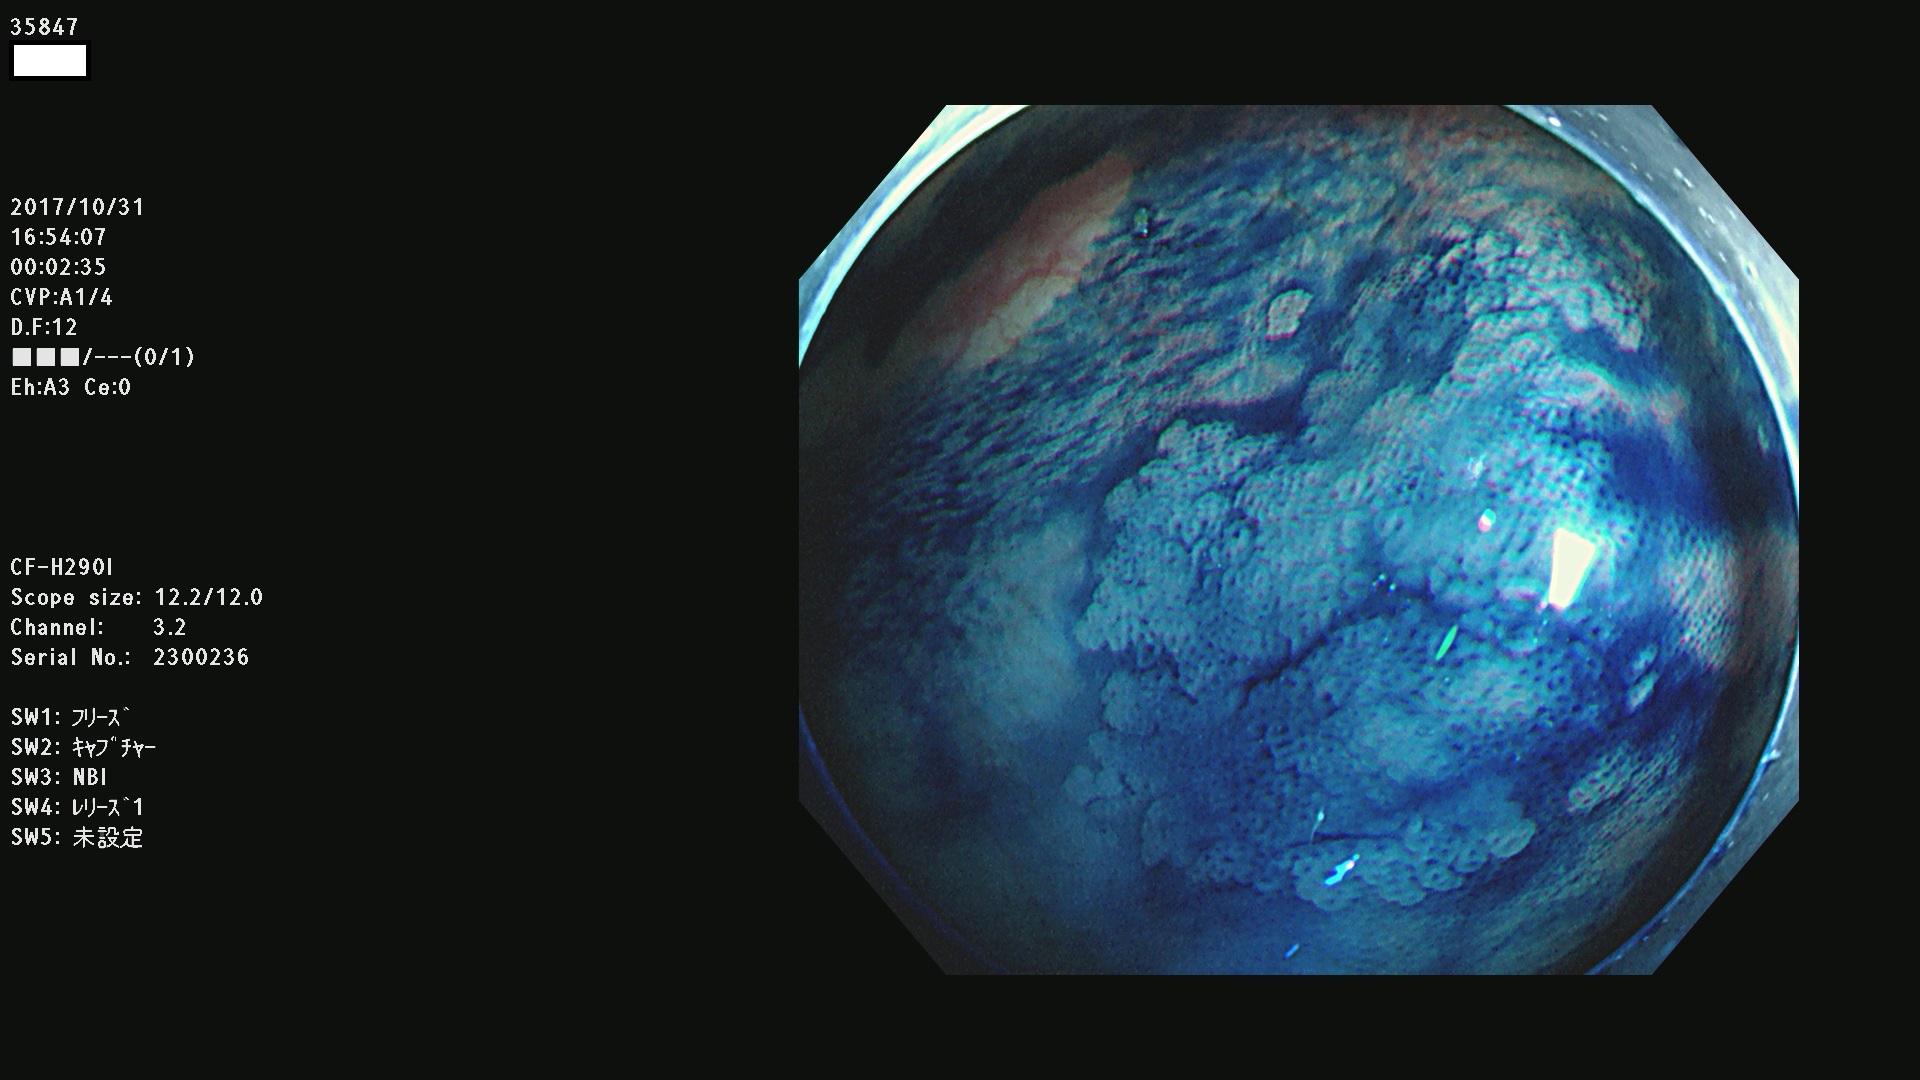

35801 35802 35806 35808 35816 35820 35821 35826 35828 35830(SSA/Pのみ) 35833 35834 35835 35837 35838 35840 35841 35843 35847 35852 35855 35857 35859 35863 35864 35865 35866 35867 35869(SSA/Pのみ) 35872 35873 35875 35878 35880 35882 35885 35886 35888 35890 35893 35895 35896 35897 35898

発見困難で危険性の高い平坦型病変(上記100名より抽出)